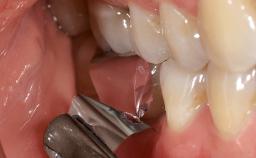

Surgical Management of Peri-Implantitis: Reconstructive Surgical Treatment with Three-Year Follow-up After Treatment

A 70-year-old female patient was referred by her general dentist to the periodontist for assessment and management of an infection associated with implant 36. The general dentist had noted suppuration on probing during examination.